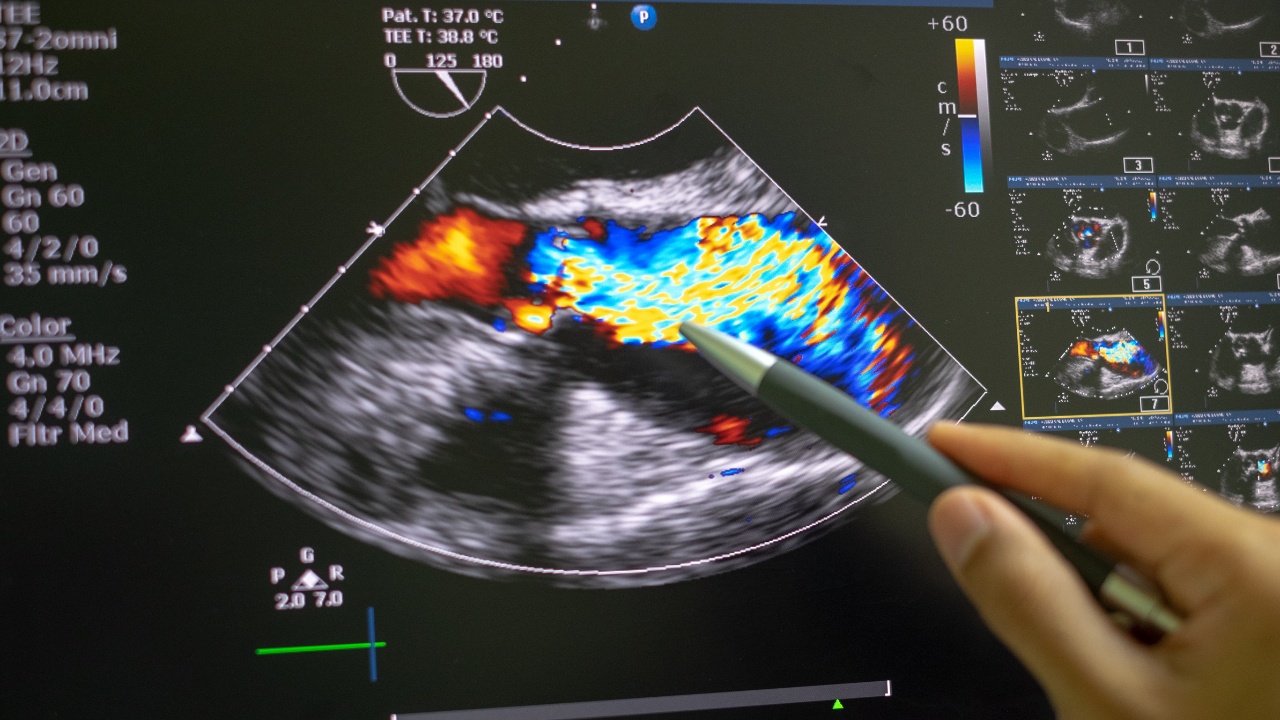

Un Doppler TSA es una ecografía Doppler de troncos supraaórticos.

Este estudio evalúa el flujo sanguíneo y el estado de las arterias que llevan sangre desde el corazón hacia el cerebro, principalmente:

- Arterias carótidas (comunes, internas y externas).

- Arterias vertebrales.

- Arterias subclavias.

- Permite medir velocidad y dirección del flujo sanguíneo.